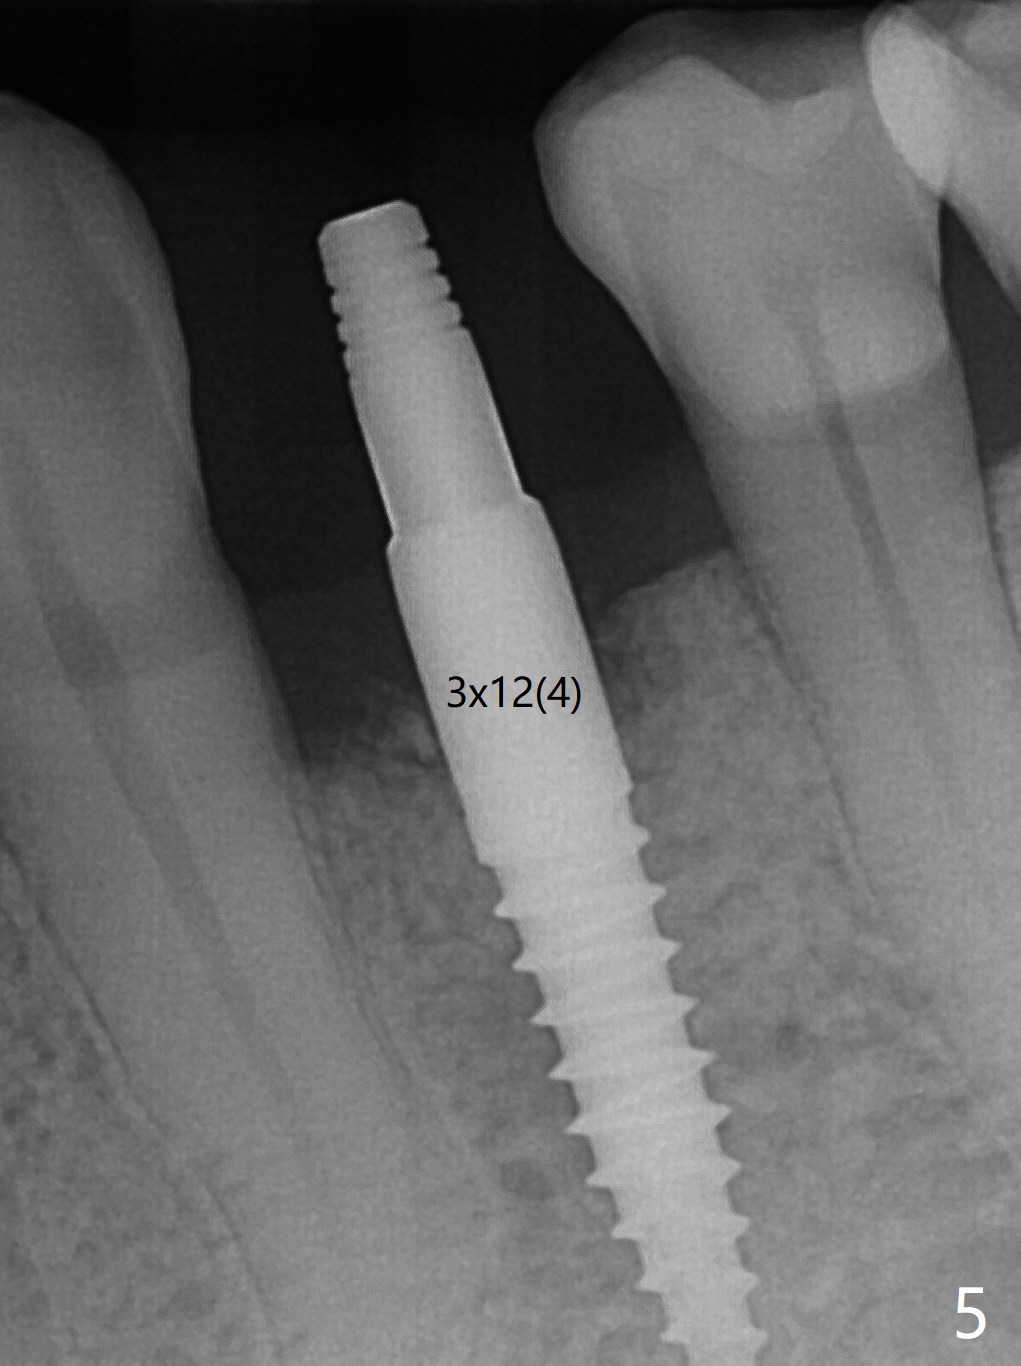

After incision at #21 (Fig.1) and flap elevation, the narrow ridge is reduced and initial osteotomy is made (Fig.2,3). Following moving the osteotomy distal, a 3x12(4) mm 1-piece implant is placed with >35 Ncm (Fig.4-6). Vanilla Graft is placed in the most concave buccal defect (Fig.1,4 *) and over the ridge reduction area (Fig.6 *). No bone loss is observed 3 months postop (Fig.7).